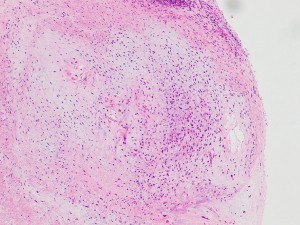

左上にはcartilage,右上にはkeratin squamous tissueがみられます。左下は繊維生組織のみdense collagenous tissueです。

生検術で胎児性癌と未熟奇形腫の混合型と診断されたために,化学療法と61.1グレイの放射線治療がなされていました。しかし,大きな松果体腫瘍が残り全摘出したものです。この子の腫瘍は治っていて元気に暮らせています。

奇形腫の照射後はいつもそうなのですが,dense collagenous tissueとfibroblastic spindle cellが組織の主体となっています。要するに肉芽腫のようなものです,ですから,手術摘出ではものすごく硬い線維性の腫瘍となっていてハサミでも切れずに難渋します。出血もしないし脳とは剥離できるのできます。放射線化学療法前の生検による組織像(悪性要素)は消失して単なる成熟奇形腫との病理診断となってしまいます。しかし,この組織のどこかに悪性度の高い細胞が潜んでいて,播種再発するなどということも経験しました。放射線治療後の病理組織診断はその後の予後の予想のためには役に立ちません。